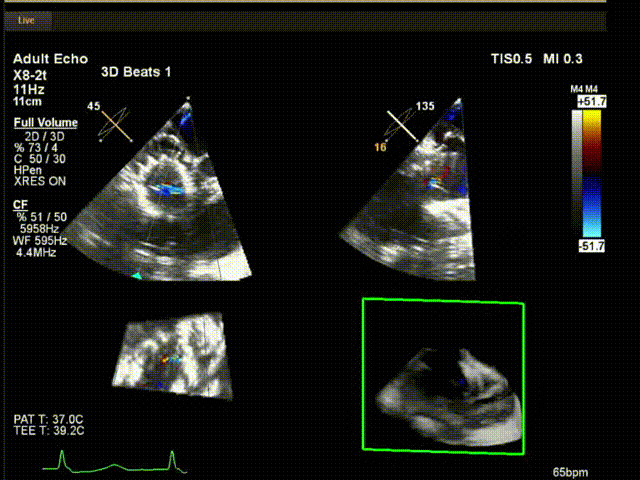

術中超聲

陸方林教授通過遠程線上帶教的方式,與林逸賢教授團隊共同完成了此次LuX-Valve Plus人工瓣膜的首例植入。術后食道超聲提示三尖瓣反流完全消失,無瓣周漏,且LuX-Valve Plus人工瓣膜的兩個夾持鍵成功抓取瓣葉,錨定牢固,人工瓣膜穩定性良好。

林逸賢教授表示:雖然此次手術難度大,患者高齡,解剖結構復雜,但LuX-Valve Plus表現出非常顯著的優勢,(1) 操作簡便,器械操作時間短(僅不足30min),器械使用流暢度和容錯率高;(2) LuX-Valve Plus輸送系統調彎性能好,術中可進行五維調整,保證了人工瓣膜良好的同軸性;(3) 術中對超聲影像的依賴程度低,使用經胃底短軸切面,配合右室流入/流出道及X-Plane切面即可相當容易地獲取相關影像,以快速推進手術進程。